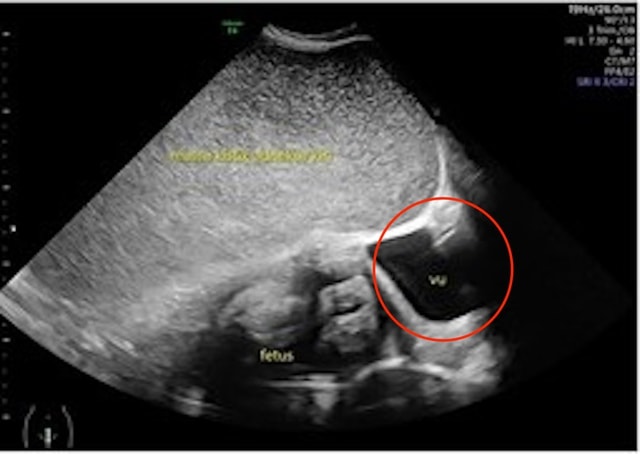

Những hình ảnh được chia sẻ bởi Need To Know cho thấy hình ảnh siêu âm khối u trước khi cắt bỏ.

Hình minh họa cho thấy vị trí của u nang, bao phủ một phần tử cung và đẩy sang một bên.

Sau lần khám bệnh thứ hai, các bác sĩ phát hiện thai nhi bắt đầu chậm phát triển – được cho là do u nang đẩy tử cung về phía bên phải bụng.